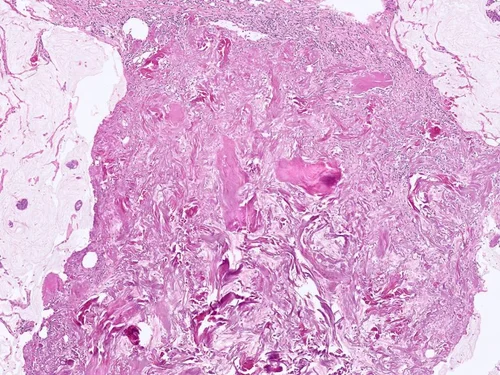

Biopsy Site Changes, Infarction of Papillary Lesion

Partial or total infarction of lesions may occur after prior procedures such as core needle biopsy or fine-needle aspiration. This is particularly true of papillary lesions and fibroepithelial lesions. As one would expect, this can confound the interpretation of the subsequent excisional specimen.

Collagen Plug

Marking devices are commonly used in core needle biopsy procedures to mark the location of the biopsy site. One type consists of a titanium clip within a bovine collagen plug.

On higher power, the collagen plug demonstrates broad bands of eosinophilic, acellular material.